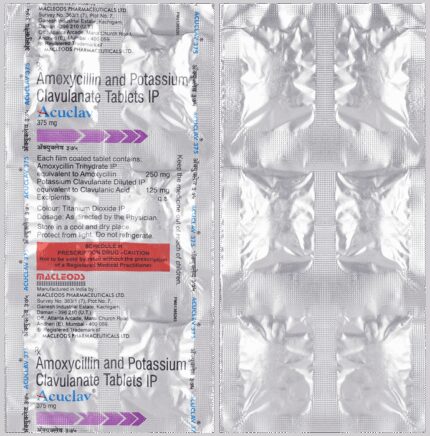

Prescription Required:Macleods Pharmaceuticals Pvt Ltd:<medicine_type>:

Amoxycillin (500mg) + Clavulanic Acid (125mg):<packagingdetail>:Strip:

10:<productform>::Store below 30°C:

Macleods Pharmaceuticals Pvt Ltd | Atlanta Arcade, Marol Church Road, Andheri (East), Mumbai – 400059, INDIA.::